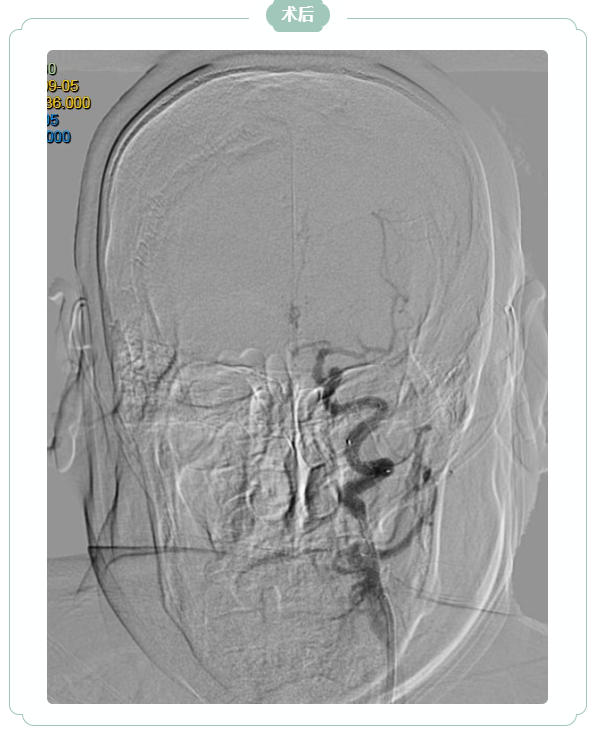

九旬的韩大爷因“言语不利、右侧肢体无力5小时”急诊入院,脑核磁显示左侧大脑半球大面积新发脑梗死,左侧颈内动脉急性闭塞。王振兴主任团队仔细研判影像发现:尽管梗死面积大,但缺血区域内仍有大量“可挽救的脑组织”——若能快速开通血管,韩大爷极有可能恢复独立生活能力。

家属透露,韩大爷2年前曾因左侧颈内动脉重度狭窄就诊于北京某医院,因血管走行极度迂曲、当时手术材料限制,未能成功植入支架。此次急性闭塞正是在“慢性狭窄基础上,因诱因导致急性闭塞”,缺血脑组织尚未完全坏死,但症状仍在持续加重。手术团队再次面临考验:韩大爷血管迂曲如“九曲十八弯”,基础病多,术中稍有不慎便可能引发致命并发症。

凭借丰富经验与先进介入技术,医生精准操控导管、导丝,克服重重障碍,历经2个多小时成功开通闭塞血管,并顺利植入一枚支架。术后第2天,韩大爷右侧肢体功能显著恢复,经过半个月综合治疗,目前已转入康复阶段,生活自理能力逐步提升。